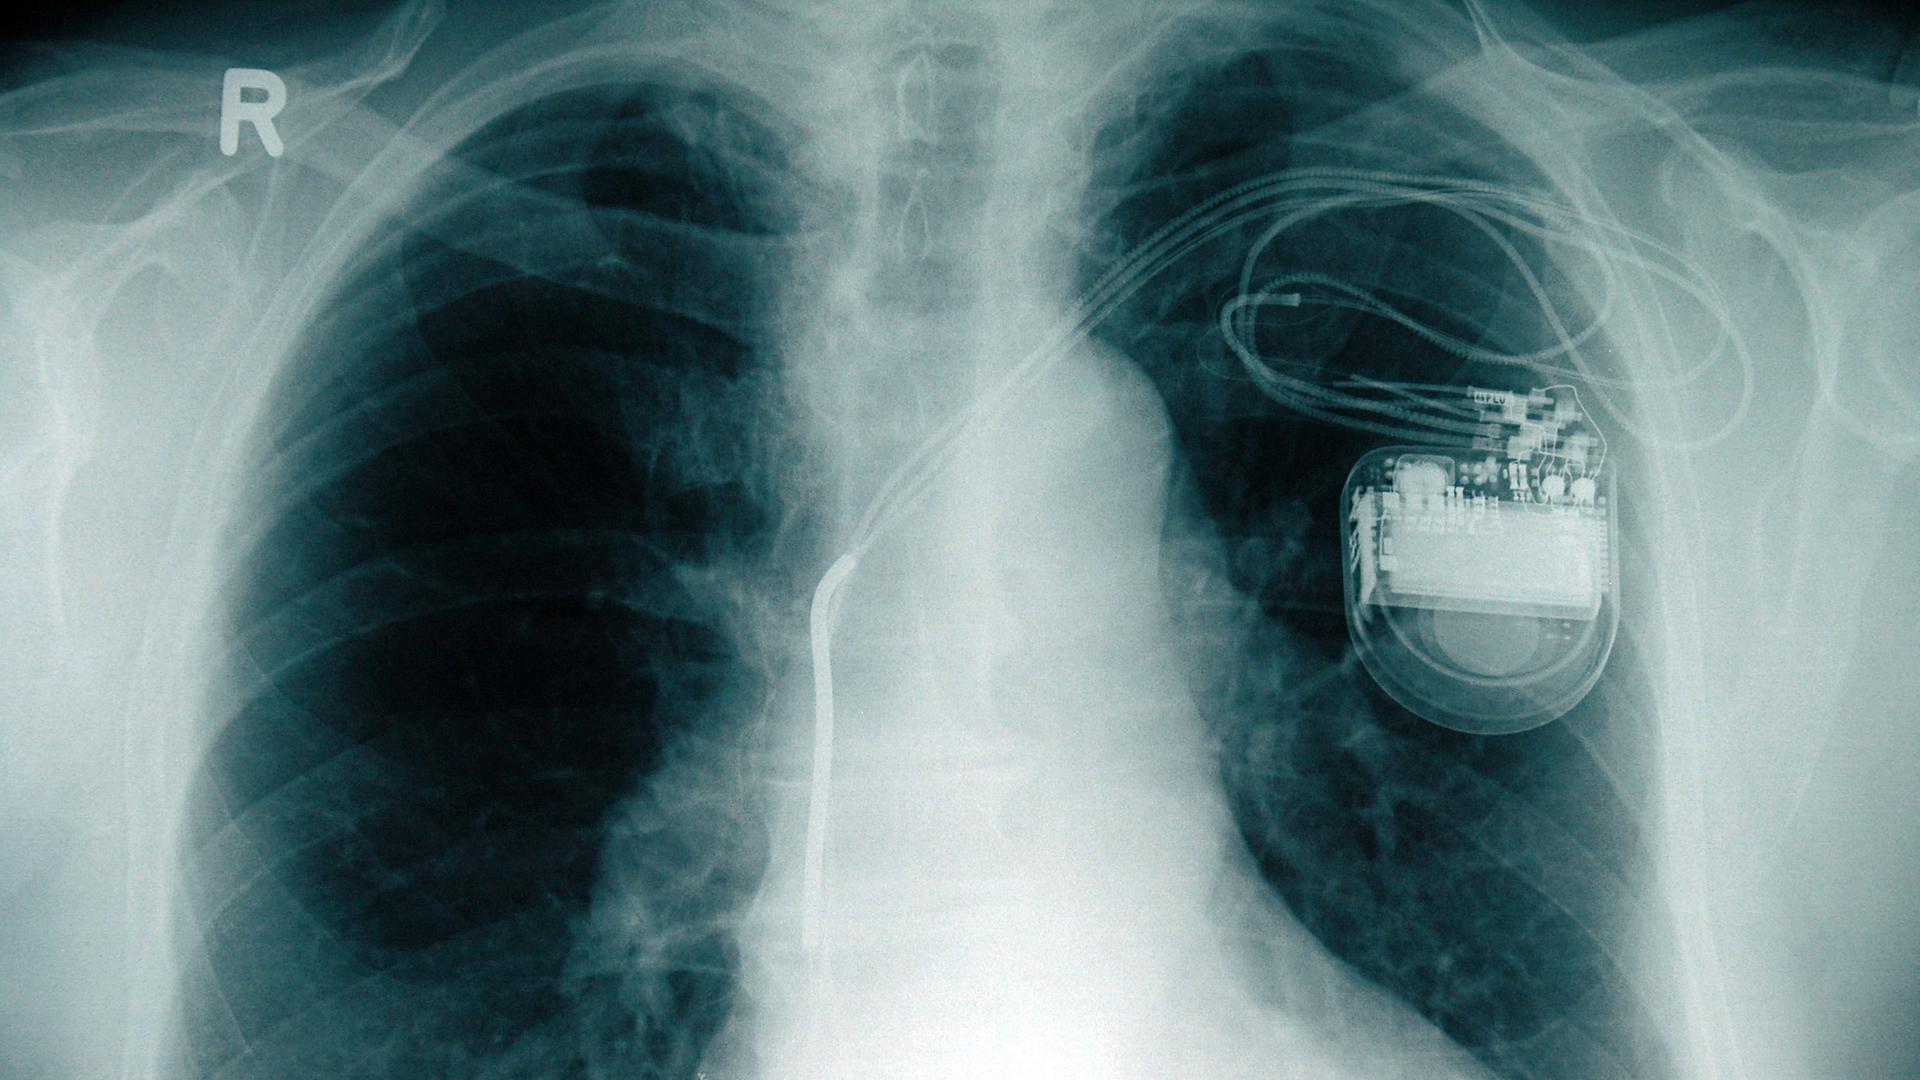

:Herzschrittmacher als neuer Schritt ins Leben

Mehr als 70.000 Menschen in Deutschland benötigen jedes Jahr einen Herzschrittmacher. Das Leben damit ist oft mit weniger Einschränkungen verbunden, als viele befürchten.

von Andreas Kürten

Archivfoto-Illustration: Röntgenbild mit Herzschrittmacher